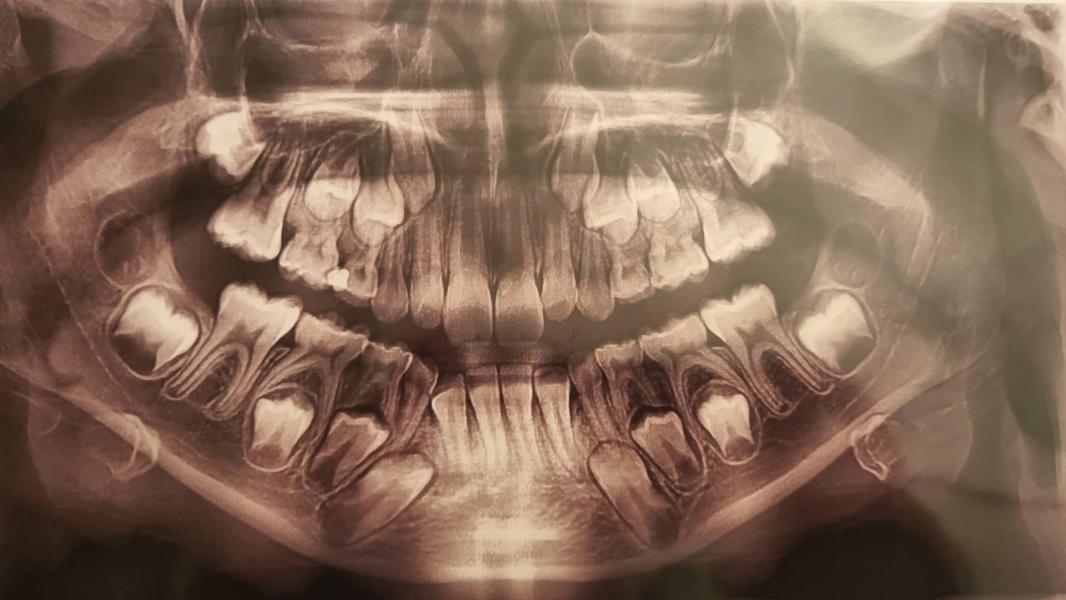

Вот такой снимок! Скученно зубы идут? Стоит расширять? Нижние клыки вообще как-то лежат...верхние клыки в нахлест. Как думаете?

@2330457, снимок не смогла найти, по нему было видно, что места для коренных зубов не хватает

@yuliyamyz спасибо. Тут и по 2ке нижней видно, что она в другой ряд даже встала

@2330457, россо на верхней челюсти и вот там по снимку видно что места не было. После расширения верхней челюсти нижняя подтягивается, но не в нашем случае.

Другая ортодонт летом говорила, что в целом можно ничего не делать, тк челюсть ещё растёт. Нюанс в том, что летняя ортодон очень крутая...но по снимку я вижу, что места вообще нет..и двойки в разворот сейчас пошли..